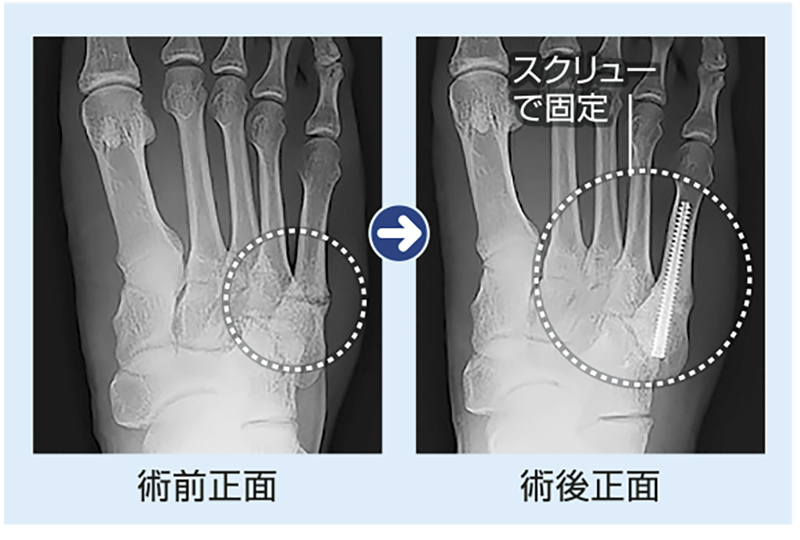

骨がつかなかったり、再発した場合は手術をしたほうがいいでしょう。手術は、骨の中にスクリューを入れて固定する方法が主流です(=写真)。ただ、成長線が残っている方はできません。この手術を行った場合、術後6週でジョギングを許可し、8週でジャンプ、ダッシュ、10週で完全復帰可能となります。